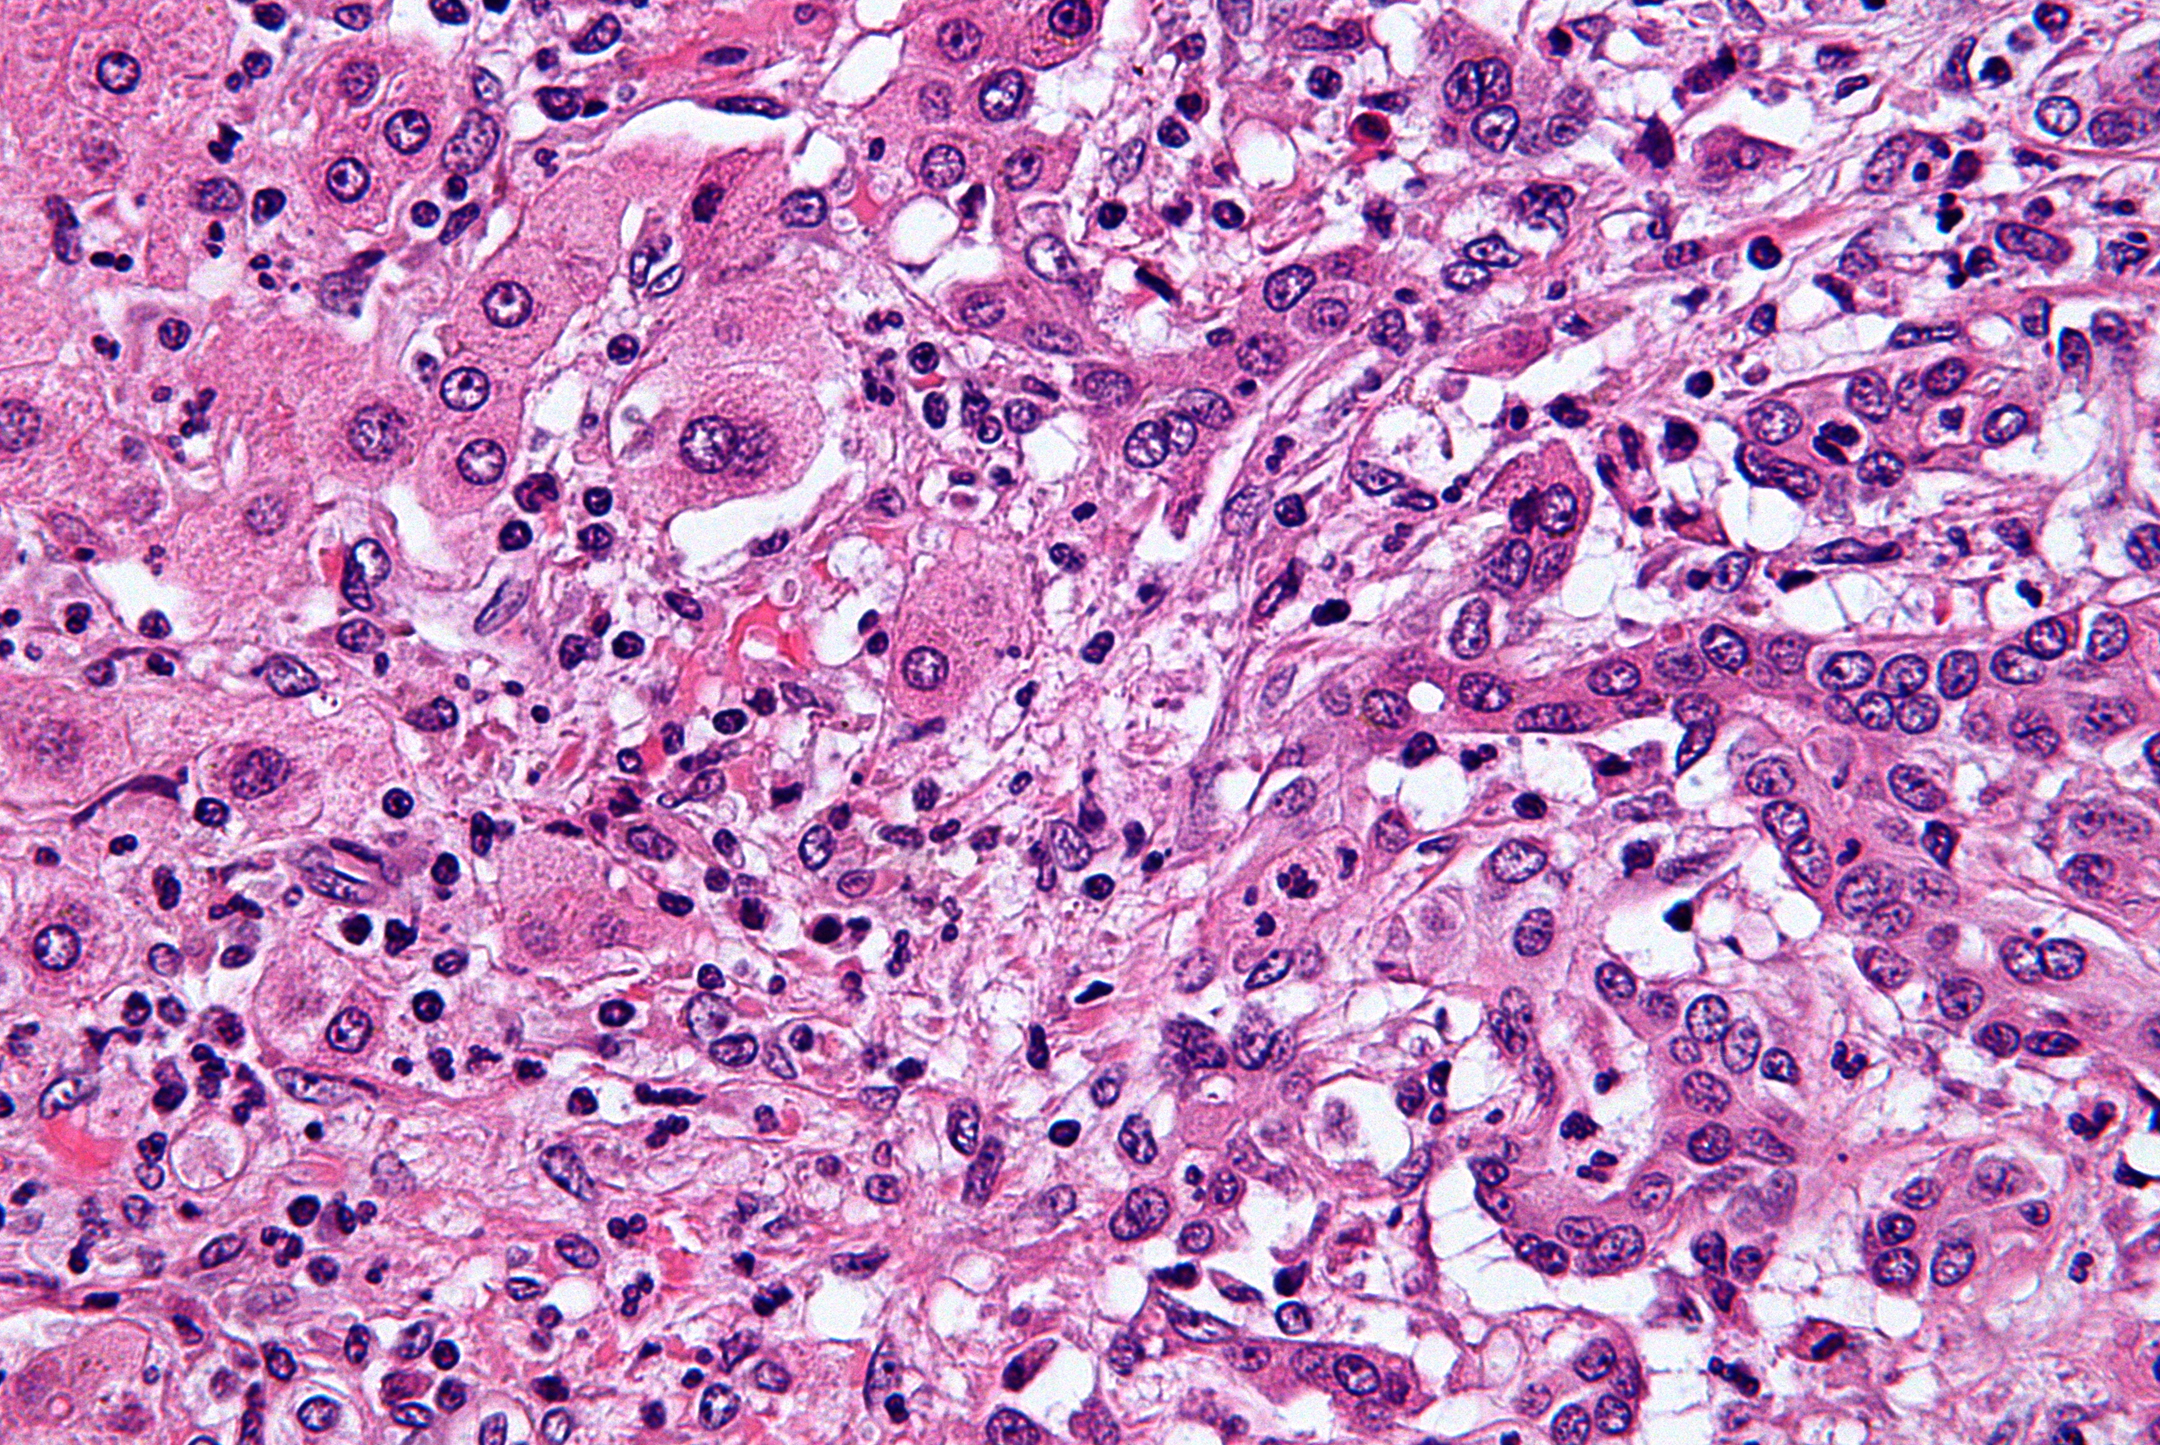

«Alcuni studi di genetica molecolare su campioni prelevati da pazienti con colangiocarcinoma hanno dimostrato che in circa il 20% di questi tumori è presente una “traslocazione” nel gene di un recettore cellulare denominato FGFR2», spiega Vincenzo Mazzaferro dell’Istituto Nazionale dei Tumori. «Poiché il gene va incontro a rottura e ricombinazione, si crea una proteina “di fusione” che stimola la cellula a proliferare senza controllo».

Il colangiocarcinoma intraepatico (iCCA) è una neoplasia ad elevata malignità che origina dalle vie biliari all’interno del fegato. La terapia più efficace è l’asportazione chirurgica del tumore (resezione o trapianto), che è tuttavia possibile solo nel 30-40% dei pazienti, con una probabilità elevata di recidiva. Nei pazienti in cui l’intervento chirurgico non è possibile o è controindicato, la cura di scelta è la chemioterapia che, tuttavia, ha un'efficacia limitata nell’arrestare la progressione tumorale. Per i pazienti non responsivi alla chemioterapia, ad oggi, non sono disponibili valide opzioni terapeutiche, con una prognosi invariabilmente fatale. Per questa fascia di pazienti, l’identificazione di una nuova cura potrà fornire un beneficio terapeutico.